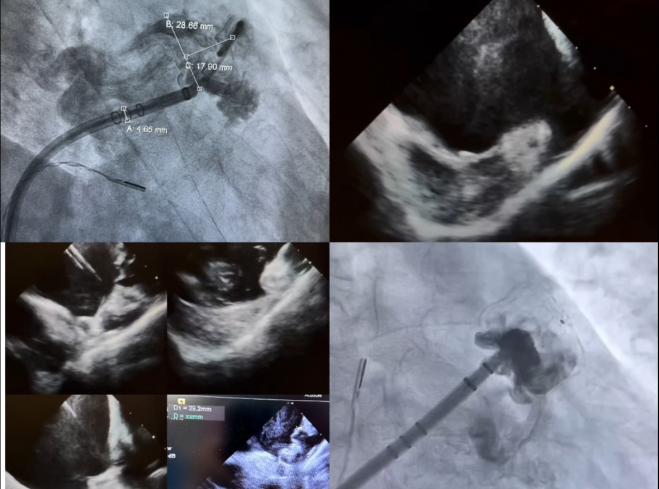

同时,科室成功为两名均发生过房颤栓塞事件的高危老年男性患者实施左心耳封堵术。其中一位患者既往诊断风湿性心脏病、心房颤动,近年反复发作3次脑栓塞事件,最近的一次脑栓塞发生在2周前,严重影响患者生命安全及生活质量。另一位患者有10余年的房颤病史,1月前发生下肢动脉栓塞,经积极治疗避免了截肢风险。两位患者均为在抗凝治疗情况下,发生房颤栓塞事件,经病情评估及全科讨论,行左心耳封堵术预防栓塞指征明确。心内三科手术团队李喆副主任医师、薛建颖主治医师、孟航主治医师、刘成峰住院医师通力合作,成功为两位房颤高栓塞风险患者完成左心耳封堵术,术后两位患者均恢复良好。

图2 左心耳封堵,房颤合并反复脑栓塞患者

图3 左心耳封堵,房颤合并下肢动脉栓塞患者